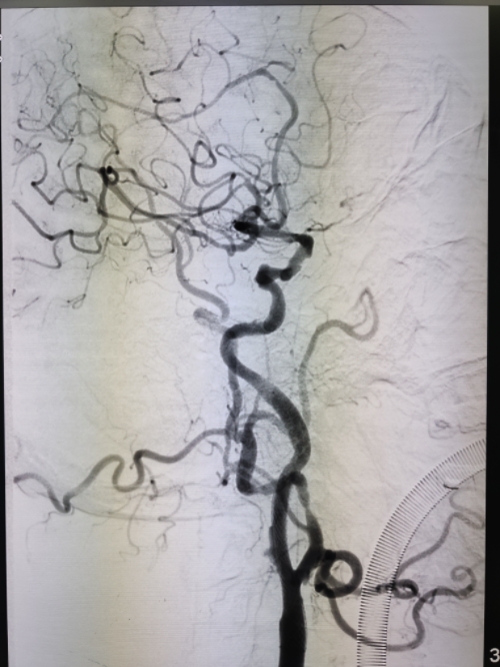

确认逆流稳定、无空气,行颈动脉造影,明确狭窄部位、长度、直径。

行多角度造影,确认:残余狭窄<10%、支架位置/形态满意、无夹层/血肿、远端血流通畅。

术后颈动脉血管狭窄完全解除